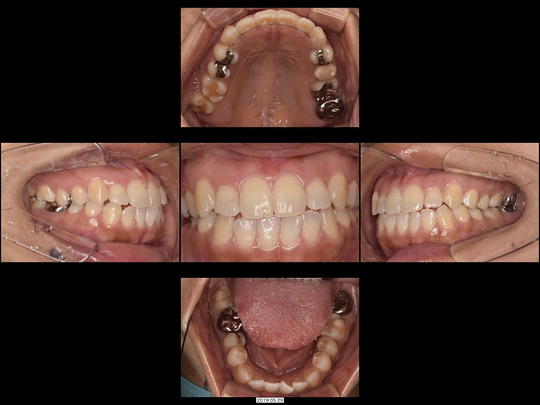

Tさん 20代 男性

矯正前

画像をクリックで拡大

矯正後

治療の説明

下前歯だけ、部分的なマウスピース型矯正装置を使った矯正治療をしました。非抜歯にて完了しています。

治療の期間・回数

9か月、12回

​費用

470,800円